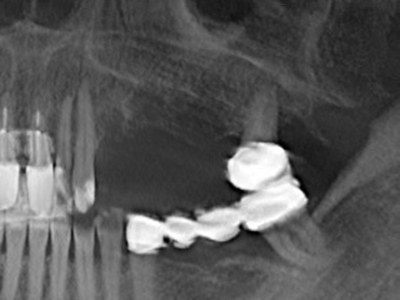

Die Präparation des lateralen Fensters bei der externen Sinusbodenelevation stellt gerade für chirurgisch unerfahrene Implantologen eine große Herausforderung dar. Die knöcherne Bedeckung der Kieferhöhle ohne eine Verletzung der darunterliegenden Schneider’schen Membran abzutragen ist dabei nur ein Teil der Operation – nach Schaffung eines ausreichenden Zugangs muss die Kieferhöhlenschleimhaut vorsichtig mobilisiert werden, um Raum für das einzubringende Material bzw. die Implantate zu schaffen. In dieser Indikation ist die Piezochirurgie zweierlei hilfreich: zum einen kann durch Verwendung diamantierter Instrumente eine selektive Knochenabtragung erfolgen und die darunter liegende Schleimhaut bleibt bei vorsichtiger Vorgehensweise intakt. Zum anderen unterstützen die Ultraschallfrequenzen zusätzlich eine komplikationslose Ablösung der Schleimhaut – sie werden durch spezielle stumpfe Ansätze in den Spaltraum zwischen Schleimhaut und Kieferhöhlenboden übertragen (Cassetta, Ricci et al. 2012, Pereira, Gealh et al. 2014) (Rickert, Vissink et al. 2013). So erscheint es nicht verwunderlich, dass in aktuellen Übersichtsarbeiten über die externe Sinusbodenelevation neben der Verwendung von rauen Implantatoberflächen und dem Einsatz von Knochenersatzmaterialien auch der Einsatz von piezoelektronischen Geräten als positiv bewertet wird (Wallace, Tarnow et al. 2012).